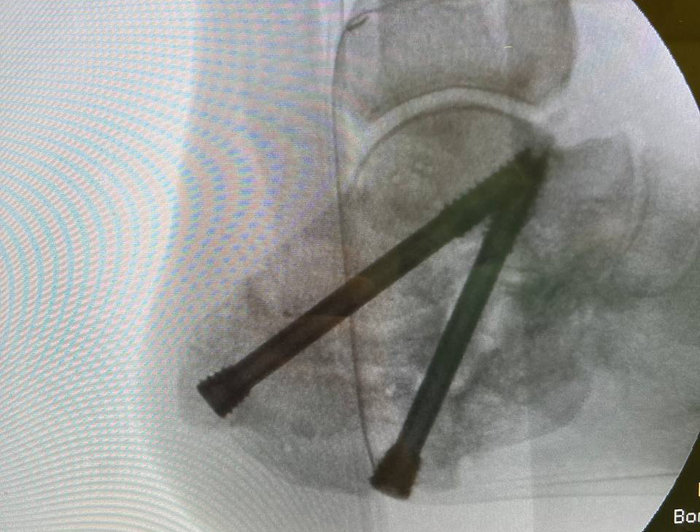

После костной пластики выполняется фиксация винтами. При этом, я аппарат на данном этапе не демонтирую. Связано это с тем, что из-за компрессии винтов, есть риск избыточного давления сдавления трансплантата, что может привести к последующей резорбции костной ткани в области контакта.

Окончательный вид.

Учитывая, что трансплантаты были установлены press-fit, то посчитал достаточным фиксацию двумя компрессионными винтами, что позволяет добиться абсолютной стабильности в зоне реартродеза.

Результаты рентгенографии, по которым видим, что анатомия пяточной кости восстановлена к максимально нативной. Также устранён субфибурялрный импиджмент синдром. Положение металлоконструкции правильнон.